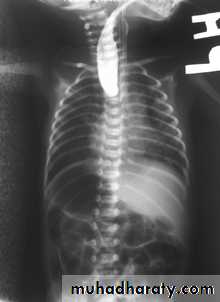

CausesEsophageal atresia

Types:• isolated atresia 8%

• Proximal fistula with distal atresia 1%

• Proximal atresia with distal fistula 85%

• Double fistula with intervening atresia 1%

• Isolated fistula [H-type] 4%